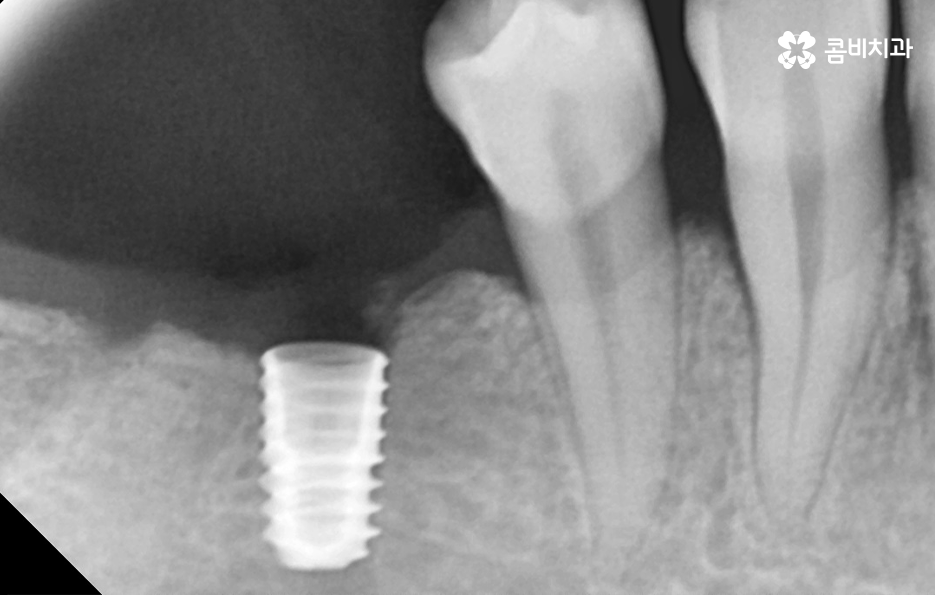

반면에 치주염이 심해져서 치조골이 녹아내리고 이미 치아의 뿌리가 보일 정도로 잇몸이 약해진 상태에는 치아 발치 후 잇몸이 충분히 회복한 뒤 임플란트를 식립할 수 있는 잇몸 뼈가 충분한지 확인 후 경우에 따라서는 뼈이식이 추가될 수 있는데요.

임플란트는 잇몸 뼈에 식립하기 때문에 치주염으로 인해 잇몸 뼈가 부족하거나 치아를 발치 후 오랜 시간이 지난 다음에 임플란트를 하게 될 경우 임플란트를 식립할 충분한 잇몸 뼈의 확보를 위해 뼈이식을 받아야 할 수 있어요

쉽게 생각하면 임플란트는 인공치근으로도 불리고 있는데 치아의 뿌리를 대신하여 임플란트가 잇몸 뼈에 식립되고 골유착 과정을 통해 단단하게 고정되어 저작력을 얻고 있는데요

40대임플란트 치료에 있어도 잇몸 뼈가 중요하고 치료 후에도 잇몸 상태를 얼마나 건강하게 관리하냐에 따라서 치료도 원활하게 진행되고 치료 후에도 건강하게 수명을 유지할 수 있다고 볼 수 있는데요